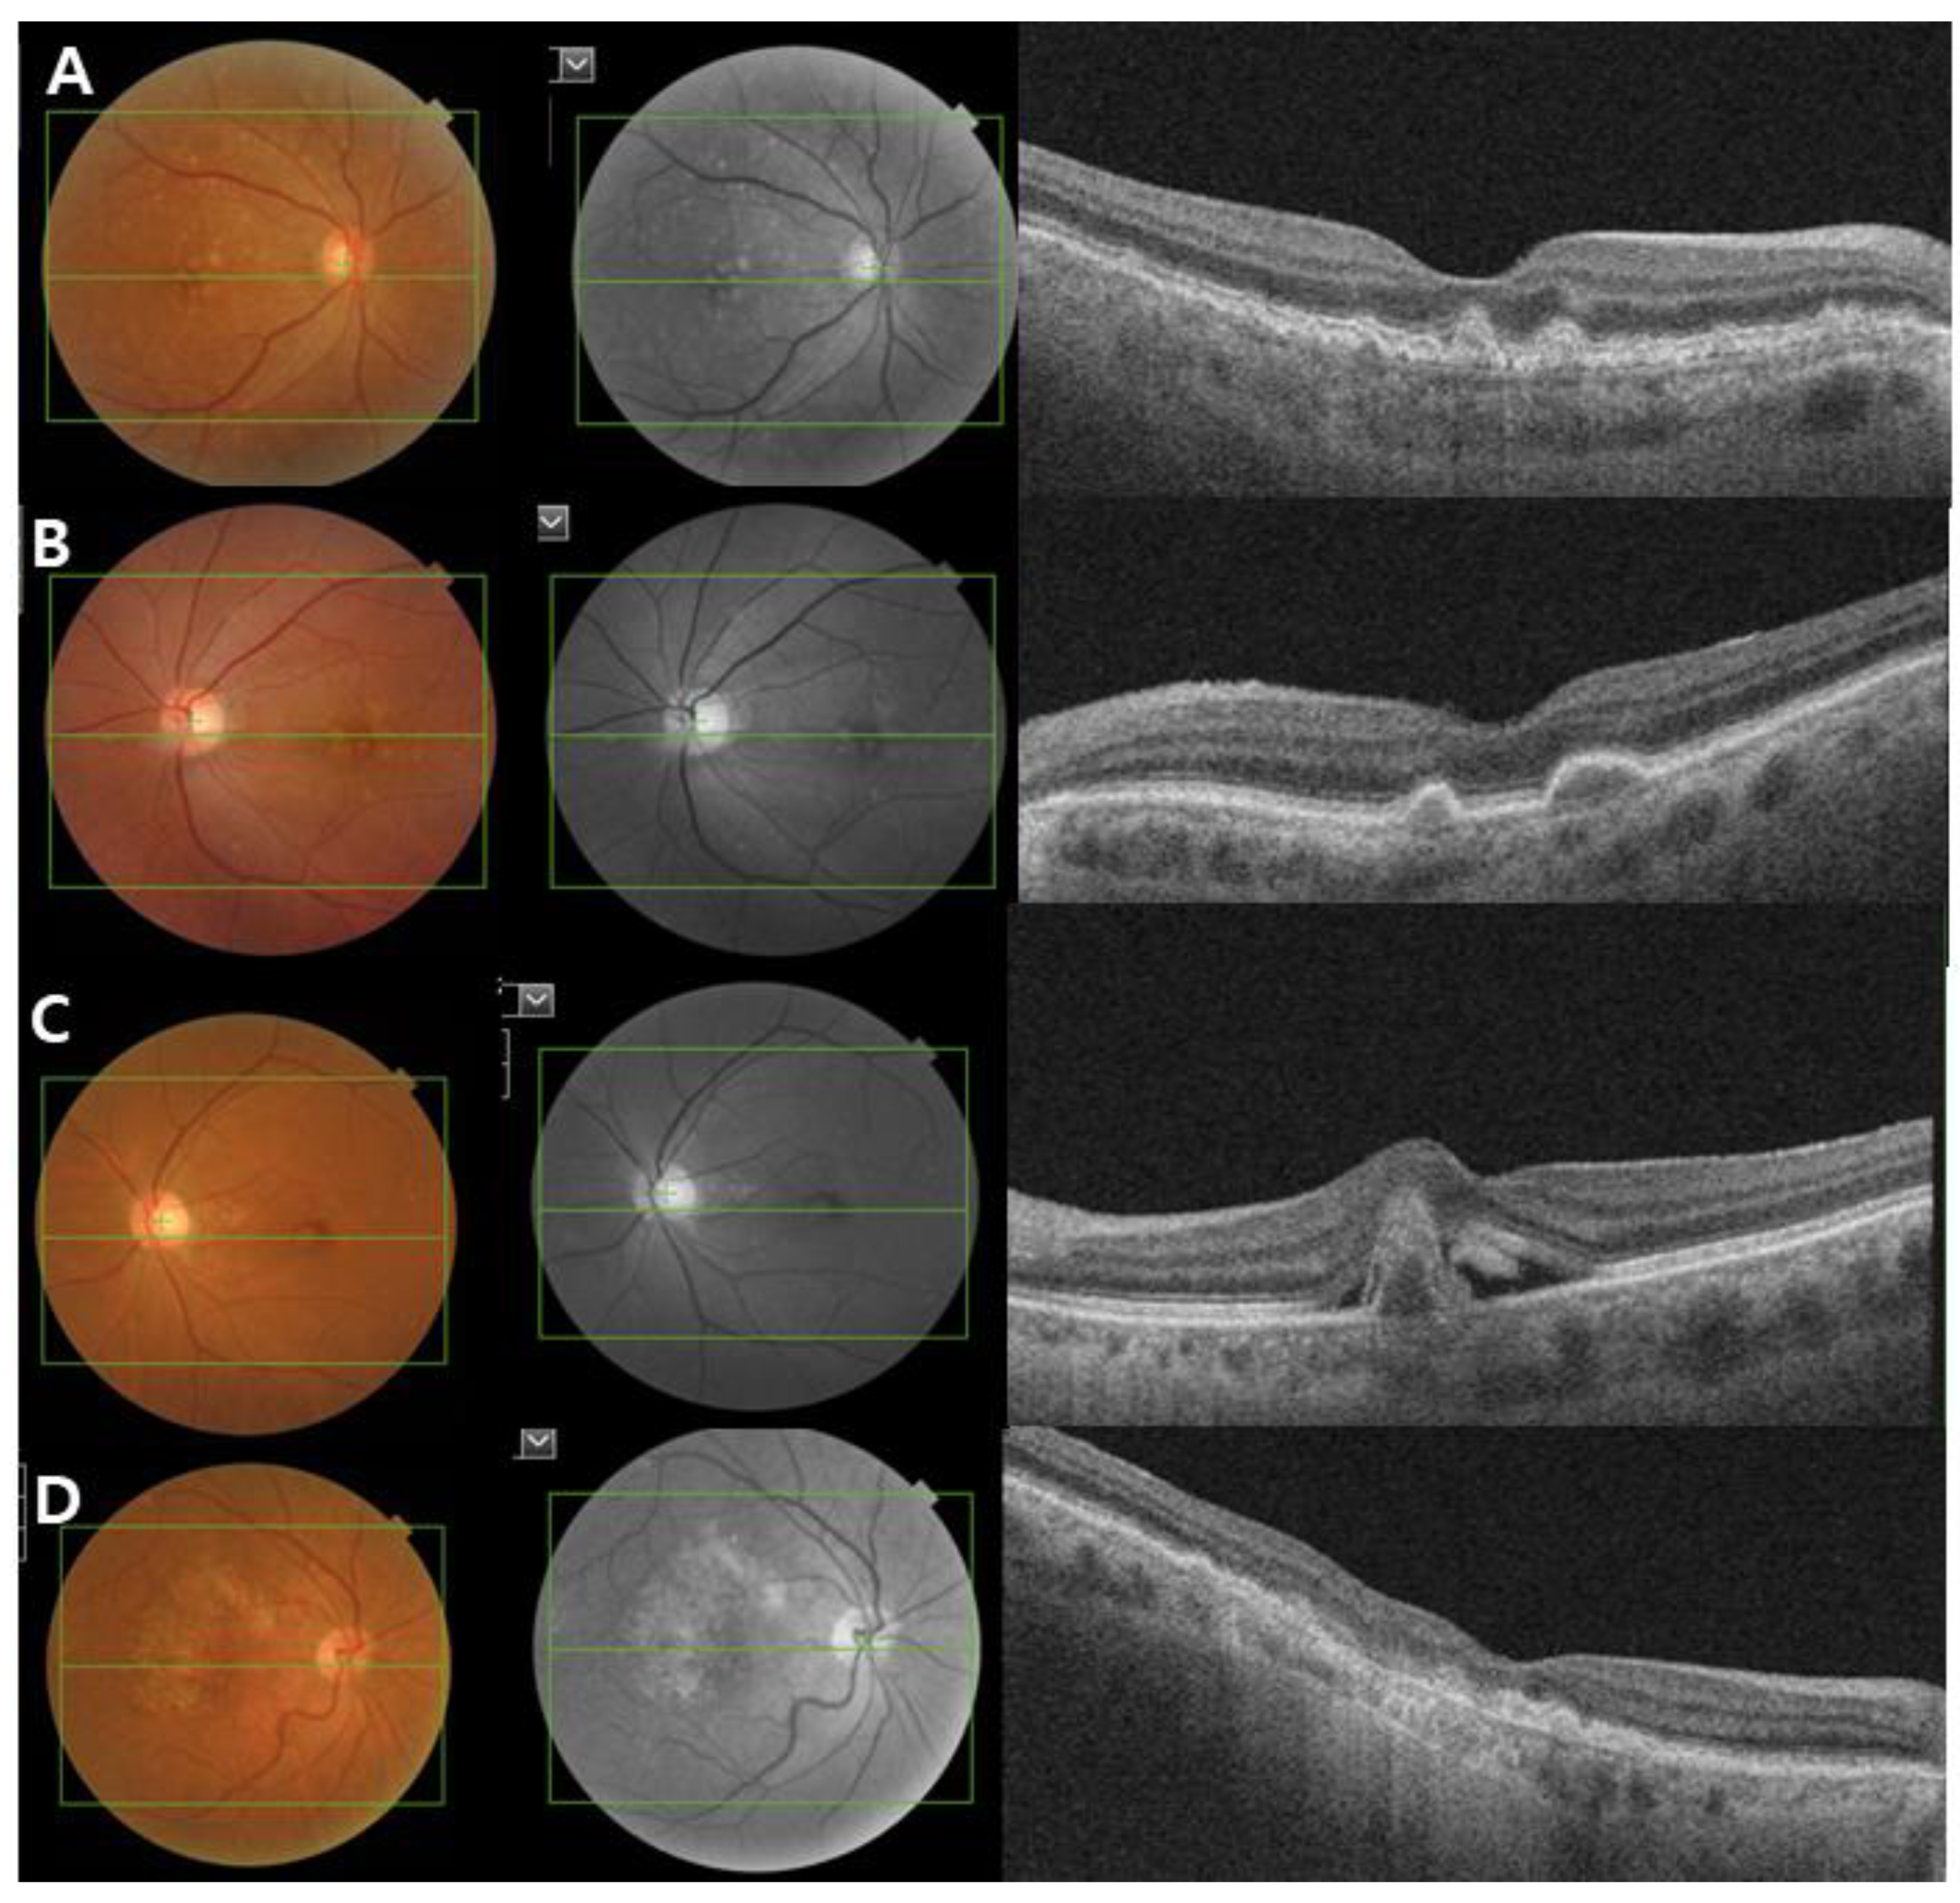

AMD is categorized into three clinical stages: early, intermediate, and late-stage AMD [14]. Early stage AMD is characterized by the presence of medium-sized drusen (>63 and ≤125 µm) without any impairment of visual function. Intermediate-stage AMD is defined as the presence of a large drusen (>125 µm) and/or abnormalities in the RPE. Late-stage AMD (advanced AMD) is classified into two clinical forms: the dry or nonexudative form (GA) and wet or exudative form (neovascular AMD). GA is defined as the irreversible loss of RPE and photoreceptor cells with progressive vision loss. Neovascular AMD is characterized by the invasion of newly immature choroidal blood vessels that break through the BM into the retina, causing exudates or hemorrhages (Figure 2).

Figure 2.

Clinical image of age-related macular degeneration (AMD). Color fundus photograph, red-free fundus photograph and swept-source optical coherence tomography (SS-OCT) images showing the characteristics of early and intermediate AMD (A,B), neovascular AMD (C) and geographic atrophy (D). (A,B) Non-neovascular AMD: Images showing small and intermediate soft drusen. (C) Neovascular AMD: subretinal fluid with subfoveal hemorrhage and a large pigment epithelial detachment. (D) Geographic atrophy: a well-demarcated area of fovea-involving retinal pigment epithelium atrophy.